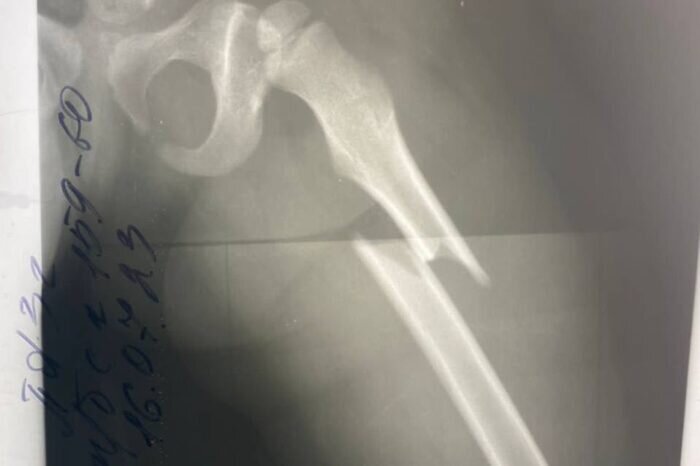

У маленькой девочки диагностировали закрытый перелом левого бедра со смещением отломков. Врачи смогли избежать лечения со скелетным вытяжением. Ребенок поступил в детскую областную больницу в конце июля. Девочка упала с качелей и получила сложный перелом бедра — серьезная патология для дальнейшего роста и развития ребенка. Ребенка успешно прооперировали и установили металлическую конструкцию. На пятые сутки малышку уже выписали. Через несколько недель девочке разрешат нагрузку на ногу, а через год удалят металлоконструкцию из бедра. Медики подчеркивают, что раньше такие случаи у детей лечились на скелетном вытяжении в течение полутора месяцев. Сегодня новые методики позволяют даже не накладывать гипс, так как перелом срастается быстрее.

Ребенка успешно прооперировали и установили металлическую конструкцию. На пятые сутки малышку уже выписали. Через несколько недель девочке разрешат нагрузку на ногу, а через год удалят металлоконструкцию из бедра.